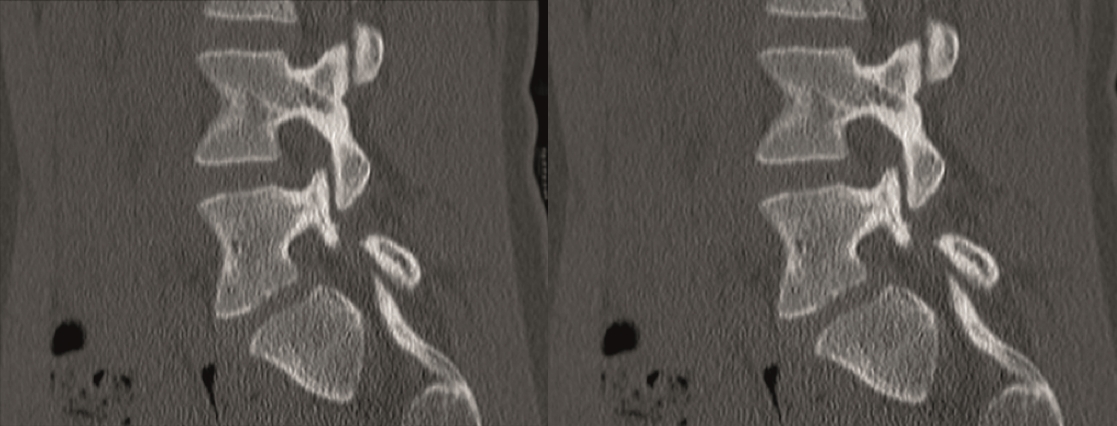

The CT showed bilateral L5 spondylolysis with grade I spondylolisthesis (Fig 10).